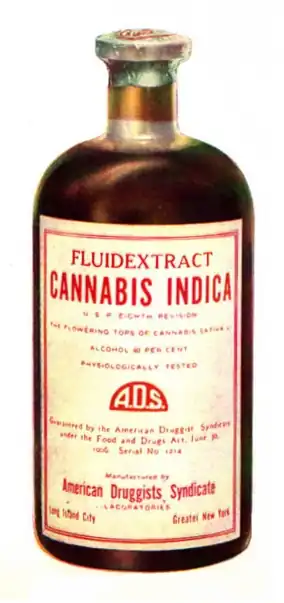

Medical

Medical cannabis, or medical marijuana, refers to the use of herbal cannabis or its preparations to treat disease or improve symptoms. There is no single agreed-upon definition (e.g., cannabinoids derived from cannabis and synthetic cannabinoid analogs are also used).[9][10][11] The rigorous scientific study of cannabis as a medicine has been hampered by production restrictions and by the fact that it is classified as an illegal drug by many governments.[12] There is some evidence suggesting cannabis can be used to reduce nausea and vomiting during chemotherapy, to improve appetite in people with HIV/AIDS, or to treat chronic pain and muscle spasms. Evidence for its use for other medical applications is insufficient for drawing conclusions about safety or efficacy.[13][14][15] There is evidence supporting the use of cannabis or its derivatives in the treatment of chemotherapy-induced nausea and vomiting, neuropathic pain, and multiple sclerosis. Lower levels of evidence support its use for AIDS wasting syndrome, epilepsy, rheumatoid arthritis, and glaucoma.[16]

The medical use of cannabis is legal only in a limited number of territories, including Canada,[17] Belgium, Australia, the Netherlands, New Zealand,[18][19] Spain, and many U.S. states. This usage generally requires a prescription, and distribution is usually done within a framework defined by local laws.[16]

Tincture

Cannabinoids can be extracted from cannabis plant matter using high-proof spirits (often grain alcohol) to create a tincture, often referred to as "green dragon".[32]: p17 Nabiximols is a branded product name from a tincture manufacturing pharmaceutical company.[184]